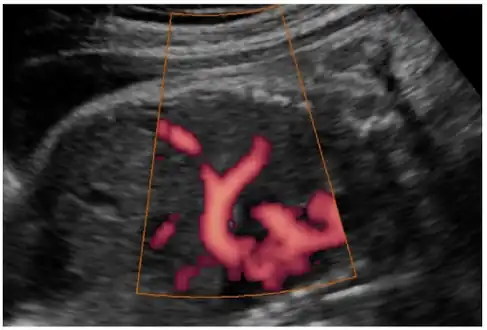

In most cases, postnatal diagnosis is done and up to 2011, only four cases are reported via prenatal diagnosis.[3] Congenital diaphragmatic hernia and intrauterine growth retardation (these two signs put the patients at the risk of afflicting with ring chromosome 15) by fetal ultrasound (Obstetric ultrasonography) at the time period of 16–24 weeks, further investigation and diagnostics (such as karyotyping) must be performed to test the possibility of ring chromosome 15.

Ultrasound finding in a fetus showing liver herniation into the thorax

Congenital diaphragmatic hernia